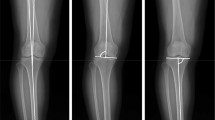

To answer the first research question, the medial and lateral tibial slope was assessed according to the protocol proposed by Hashemi et al. [5]. Initially, the first proximal slice on transverse MR images that showed the entire tibial head was identified (Fig. 1). In this transverse image, the corresponding sagittal slice located most closely to the tibial head centre was determined (solid line in Fig. 1). This sagittal plane, which is shown in Fig. 2a, was then used to identify the longitudinal axis of the tibial diaphysis. The longitudinal axis was defined as the midpoint of the anterior–posterior width of the tibia at two points located 4–5 cm distally to the joint line and as distally as possible. The conjugation line of these two points represents the longitudinal axis of the tibia in the sagittal plane. To measure the medial and lateral tibial slope, the longitudinal axis was assigned to the corresponding planes in the centre of the medial tibial plateau and in the centre of the lateral tibia plateau, shown as dashed lines in Fig. 1. Again, the corresponding planes were reproduced in the medial and lateral sagittal image (Fig. 2b, c). The conjugation line between the peak anterior and posterior points of the bony tibia plateau measured the inclination of the tibial slope perpendicular to the longitudinal axis of the tibia. The tibial slope was defined as positive if the peak anterior point lay above the peak posterior point and was defined as negative if the posterior point lay above the anterior point.

First transverse MR image in craniocaudal direction that shows the entire tibial head. In this transverse image, the corresponding sagittal slices located most closely to the tibial head centre (solid line) and in the centre of the medial and lateral tibial plateau (dashed lines) were determined. Similarly, the corresponding coronal section located most closely to the tibial head centre (dotted line) was established

The sagittal plane that represents the corresponding image to the solid line in Fig. 1 is shown in (a). This image was used to identify the longitudinal axis of the tibial diaphysis. The longitudinal axis was defined as the midpoint of the anterior–posterior width of the tibia at two points located 4–5 cm distally to the joint line and as distally as possible. To measure the medial and lateral tibial slope, the longitudinal axis was assigned to the corresponding planes in the centre of the lateral tibial plateau (b) and in the centre of the medial tibia plateau (c) as shown as dashed lines in Fig. 1. The conjugation line between the peak anterior and posterior points of the tibia plateau measured the inclination of the tibial slope perpendicular to the longitudinal axis of the tibia

A comparable method was used to measure the aDLFA and mPMTA, according to Paley et al. [13]. First, the longitudinal axis of the tibia in the frontal plane was established referencing most closely to the centre of the tibial head in the corresponding transverse image (dotted line in Fig. 1). Again, the longitudinal axis was defined as the midpoint of the medial-to-lateral width of the tibia as distally as possible and at the midpoint of the tibial head. A similar approach was used to establish the diaphyseal axis of the femur in the coronal plane. The aDLFA and mPMTA were then measured as the angle between the longitudinal axis of the femur and tibia and the joint line represented by the most distally located points of the femoral condyles, and the peak points of the medial and lateral tibial plateau, respectively (Fig. 3a, b).

The longitudinal axis of the femur and the tibia was established in the frontal plane referencing most closely to the centre of the tibial head in the corresponding transverse image (dotted line in Fig. 1). The longitudinal axis was defined as the midpoint of the medial-to-lateral width of the tibia as distally as possible and at the midpoint of the tibial head. A similar approach was used to establish the diaphyseal axis of the femur in the coronal plane. The aDLFA and mPMTA was then measured as the angle between the longitudinal axis of the femur and tibia and the joint line represented by the most distally located points of the femoral condyles, and the peak points of the medial and lateral tibial plateau. aDLFA anatomical distal lateral femur angle, mPMTA mechanical proximal medial tibial angle